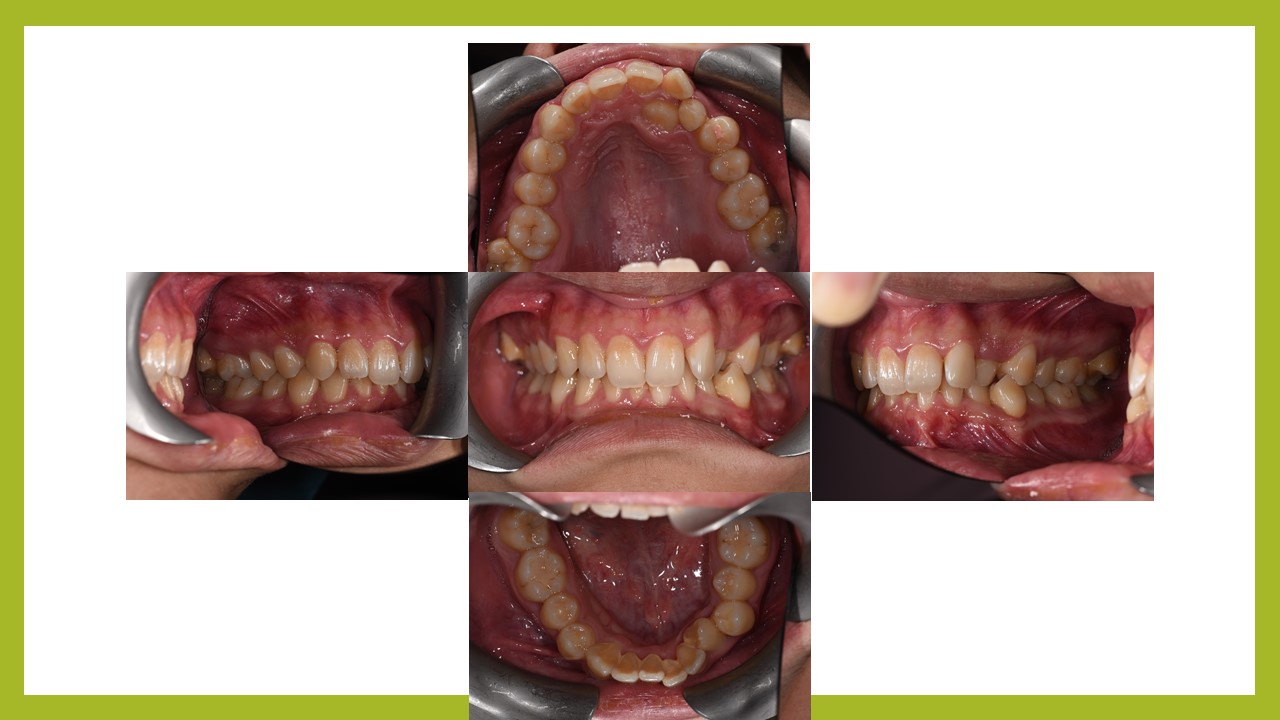

何先生因為有牙齒卡在裡面,去他家診所評估需要拔牙。後來經林醫師檢查過後,認為不須拔牙就可把牙齒排列整齊,何先生接受了不拔牙矯正。